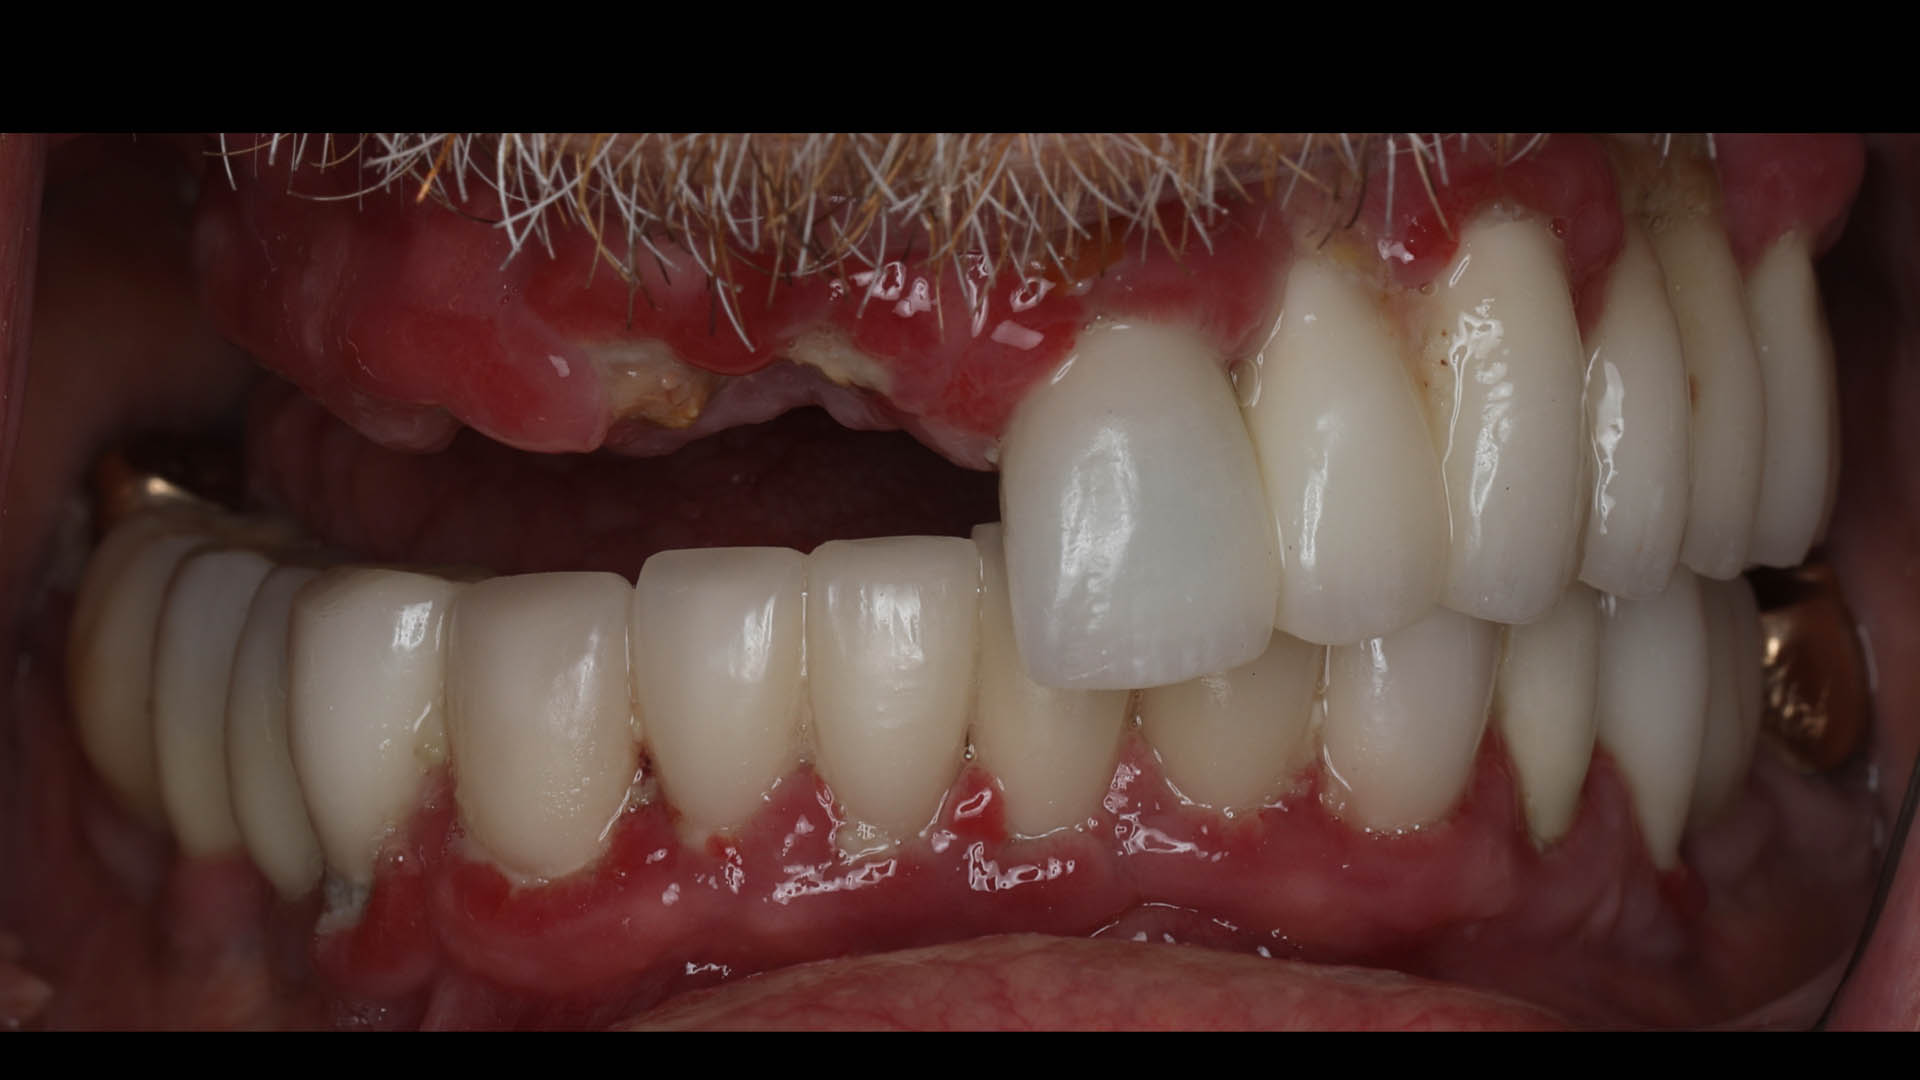

Take a glimpse into the magic of Coral Gables Dentistry through our before and after pictures. See firsthand the incredible smile makeover transformations that have brought confidence and joy to our patients.